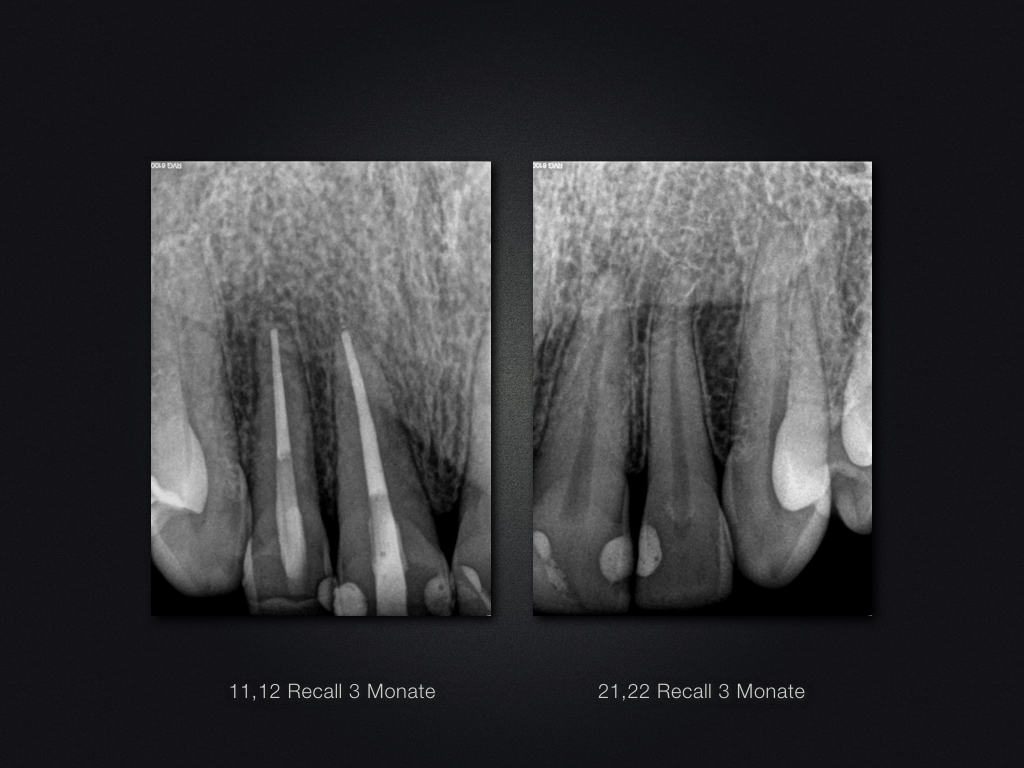

Recall nach Frontzahntrauma